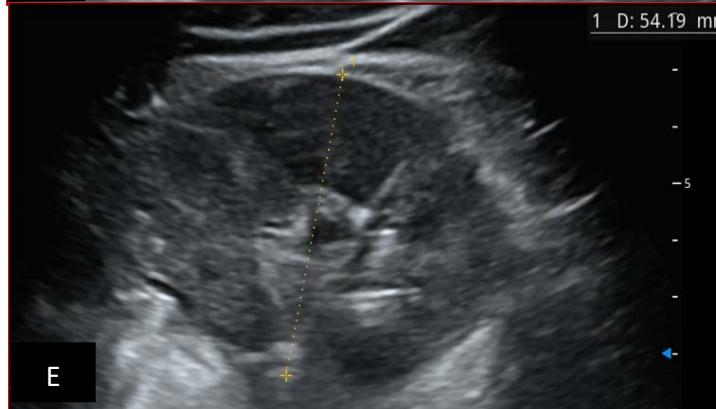

Figure 5: Abdominopelvic ultrasound control after 6 courses of chemotherapy in the same 3 year old patient with a ruptured left renal nephroblastoma; Images A, F, G, and H: show regression of the solid, endo and exo renal, left nephroblastoma mass treated with 6 courses of chemotherapy (current volume 430 ml vs) Images: B, C, and: show persistence of thrombotic permeation pan vena cava and ipsilateral renal. Image E: shows a volumetric regression of the intra-lesional hematic collection, at the tumor rupture estimated at 34.49 ml VS, Image I: represents the right kidney in B mode which is of normal echoculture. Source: Dr. Frederick Tshibasu Tshienda database.